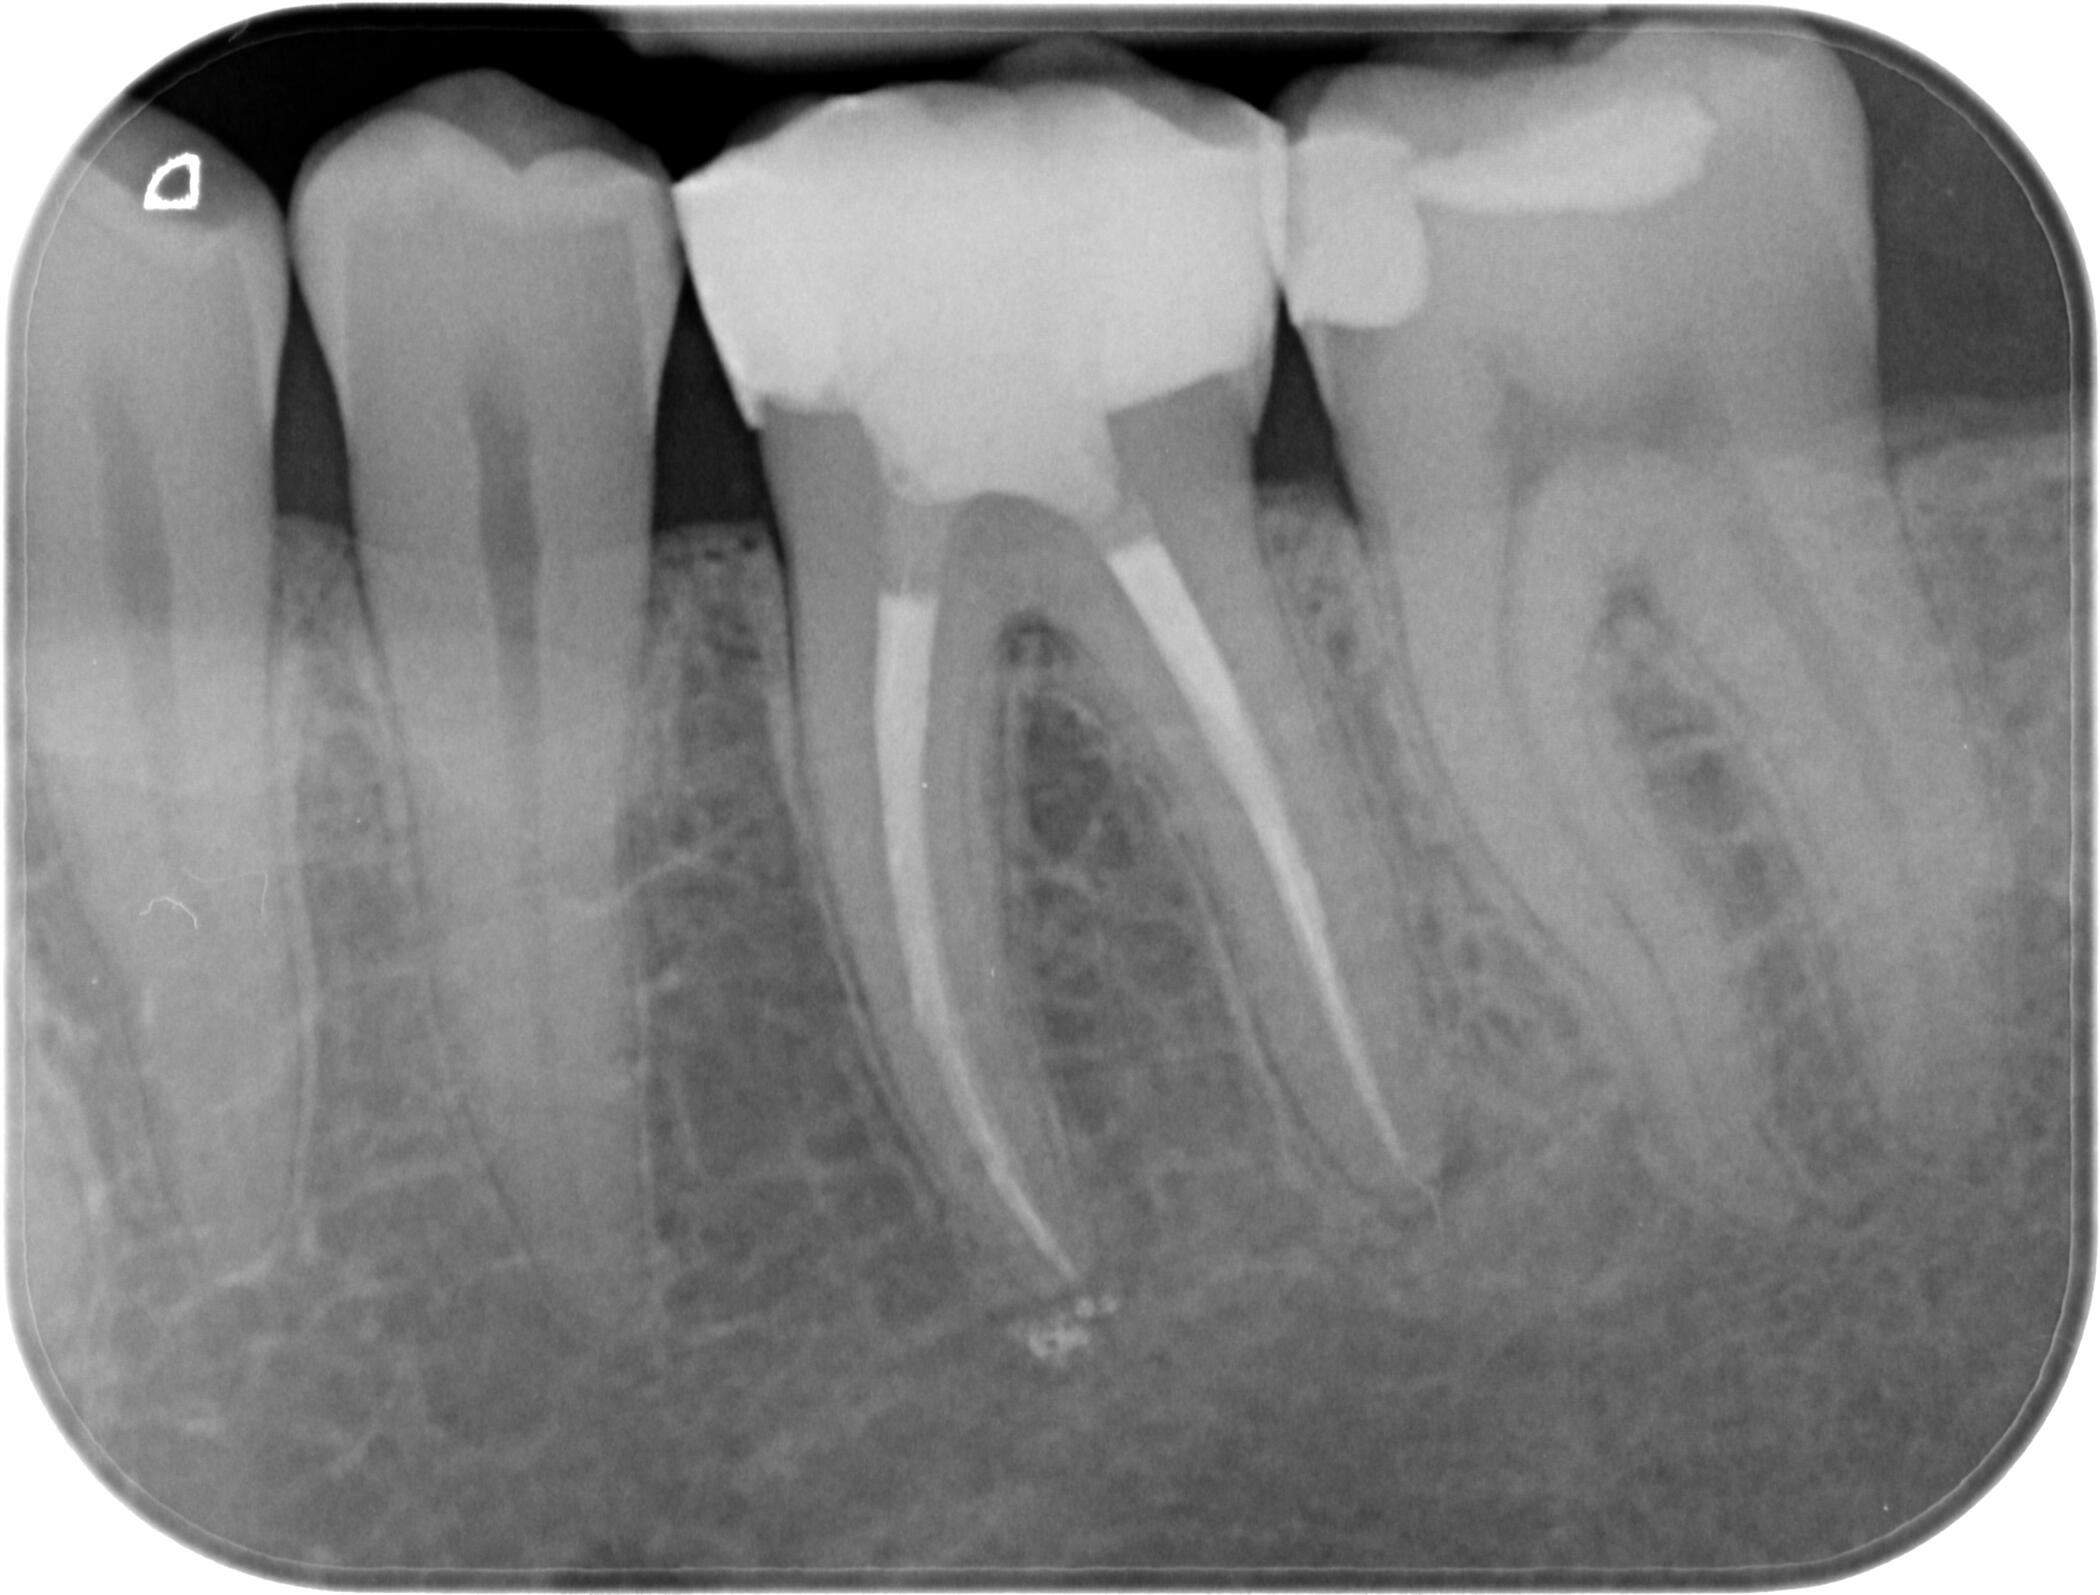

Периапикална / Сегментна рентгенография